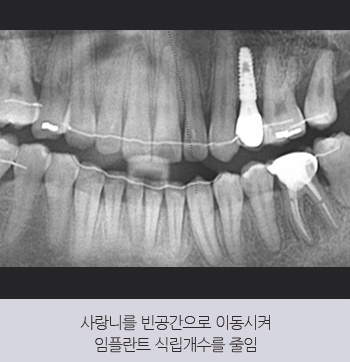

30대 남성 환자분이 다른 치과에서

5개 임플란트를 권유받고 내원하셨습니다.

본원에서는 돌출입을 개선하는

교정 치료를 함께 진행하여

기존 치아를 활용할 수 있도록 유도하였고,

사랑니를 이동시켜

빈 공간을 채우는 방법을 적용하였습니다.

그 결과, 식립 개수를

5개에서 1개로 줄일 수 있었습니다.